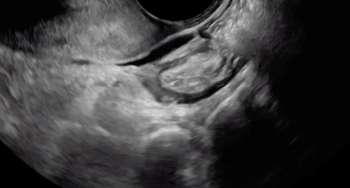

In this clip, fluid within the rectouterine pouch introduced following saline-infusion sonoPODography allows for appreciation of adhesions and a peritoneal pocket (enclosed fluid due to a defect in the peritoneum). These are two classic features of superficial endometriosis.

Although not clearly depicted in this clip, deep endometriosis likely is present posterior to the uterus at the level of the internal cervical os, as demonstrated by the irregular, hypoechoic area.